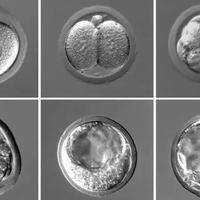

许多家庭希望通过试管婴儿技术生出一对龙凤胎,即一男一女的双胞胎。试管婴儿通过体外受精和胚胎移植,可以增加多胎妊娠的几率,但龙凤胎的性别组合并非总能控制,需要了解技术原理和潜在风险。这个过程涉及医学、伦理和概率因素,不是简单的“定制”服务。大家好,今天我们来聊聊试管婴儿和龙凤胎的事儿。有人问:试管能龙凤胎吗?答案是:有可能,但不是绝对的! 试管婴儿技术,简单说就是把精子和卵子在实验室里结合成胚胎,再...